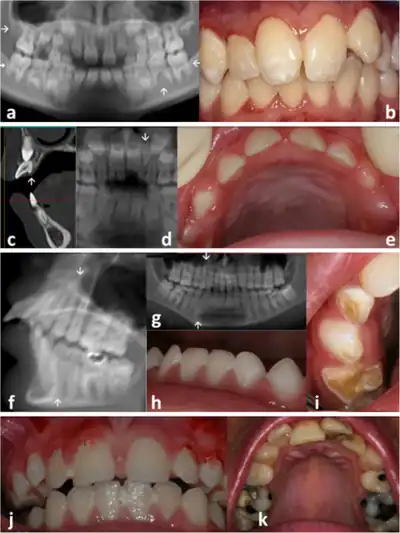

a) Three congenitally missing second permanent molars b) screwdriver shape incisors c) hyper developed cingulum d) microdont conical upper left lateral incisor (arrow) e) microdontia primary dentition f-i) enamel hypoplasia j-k) dental crowding